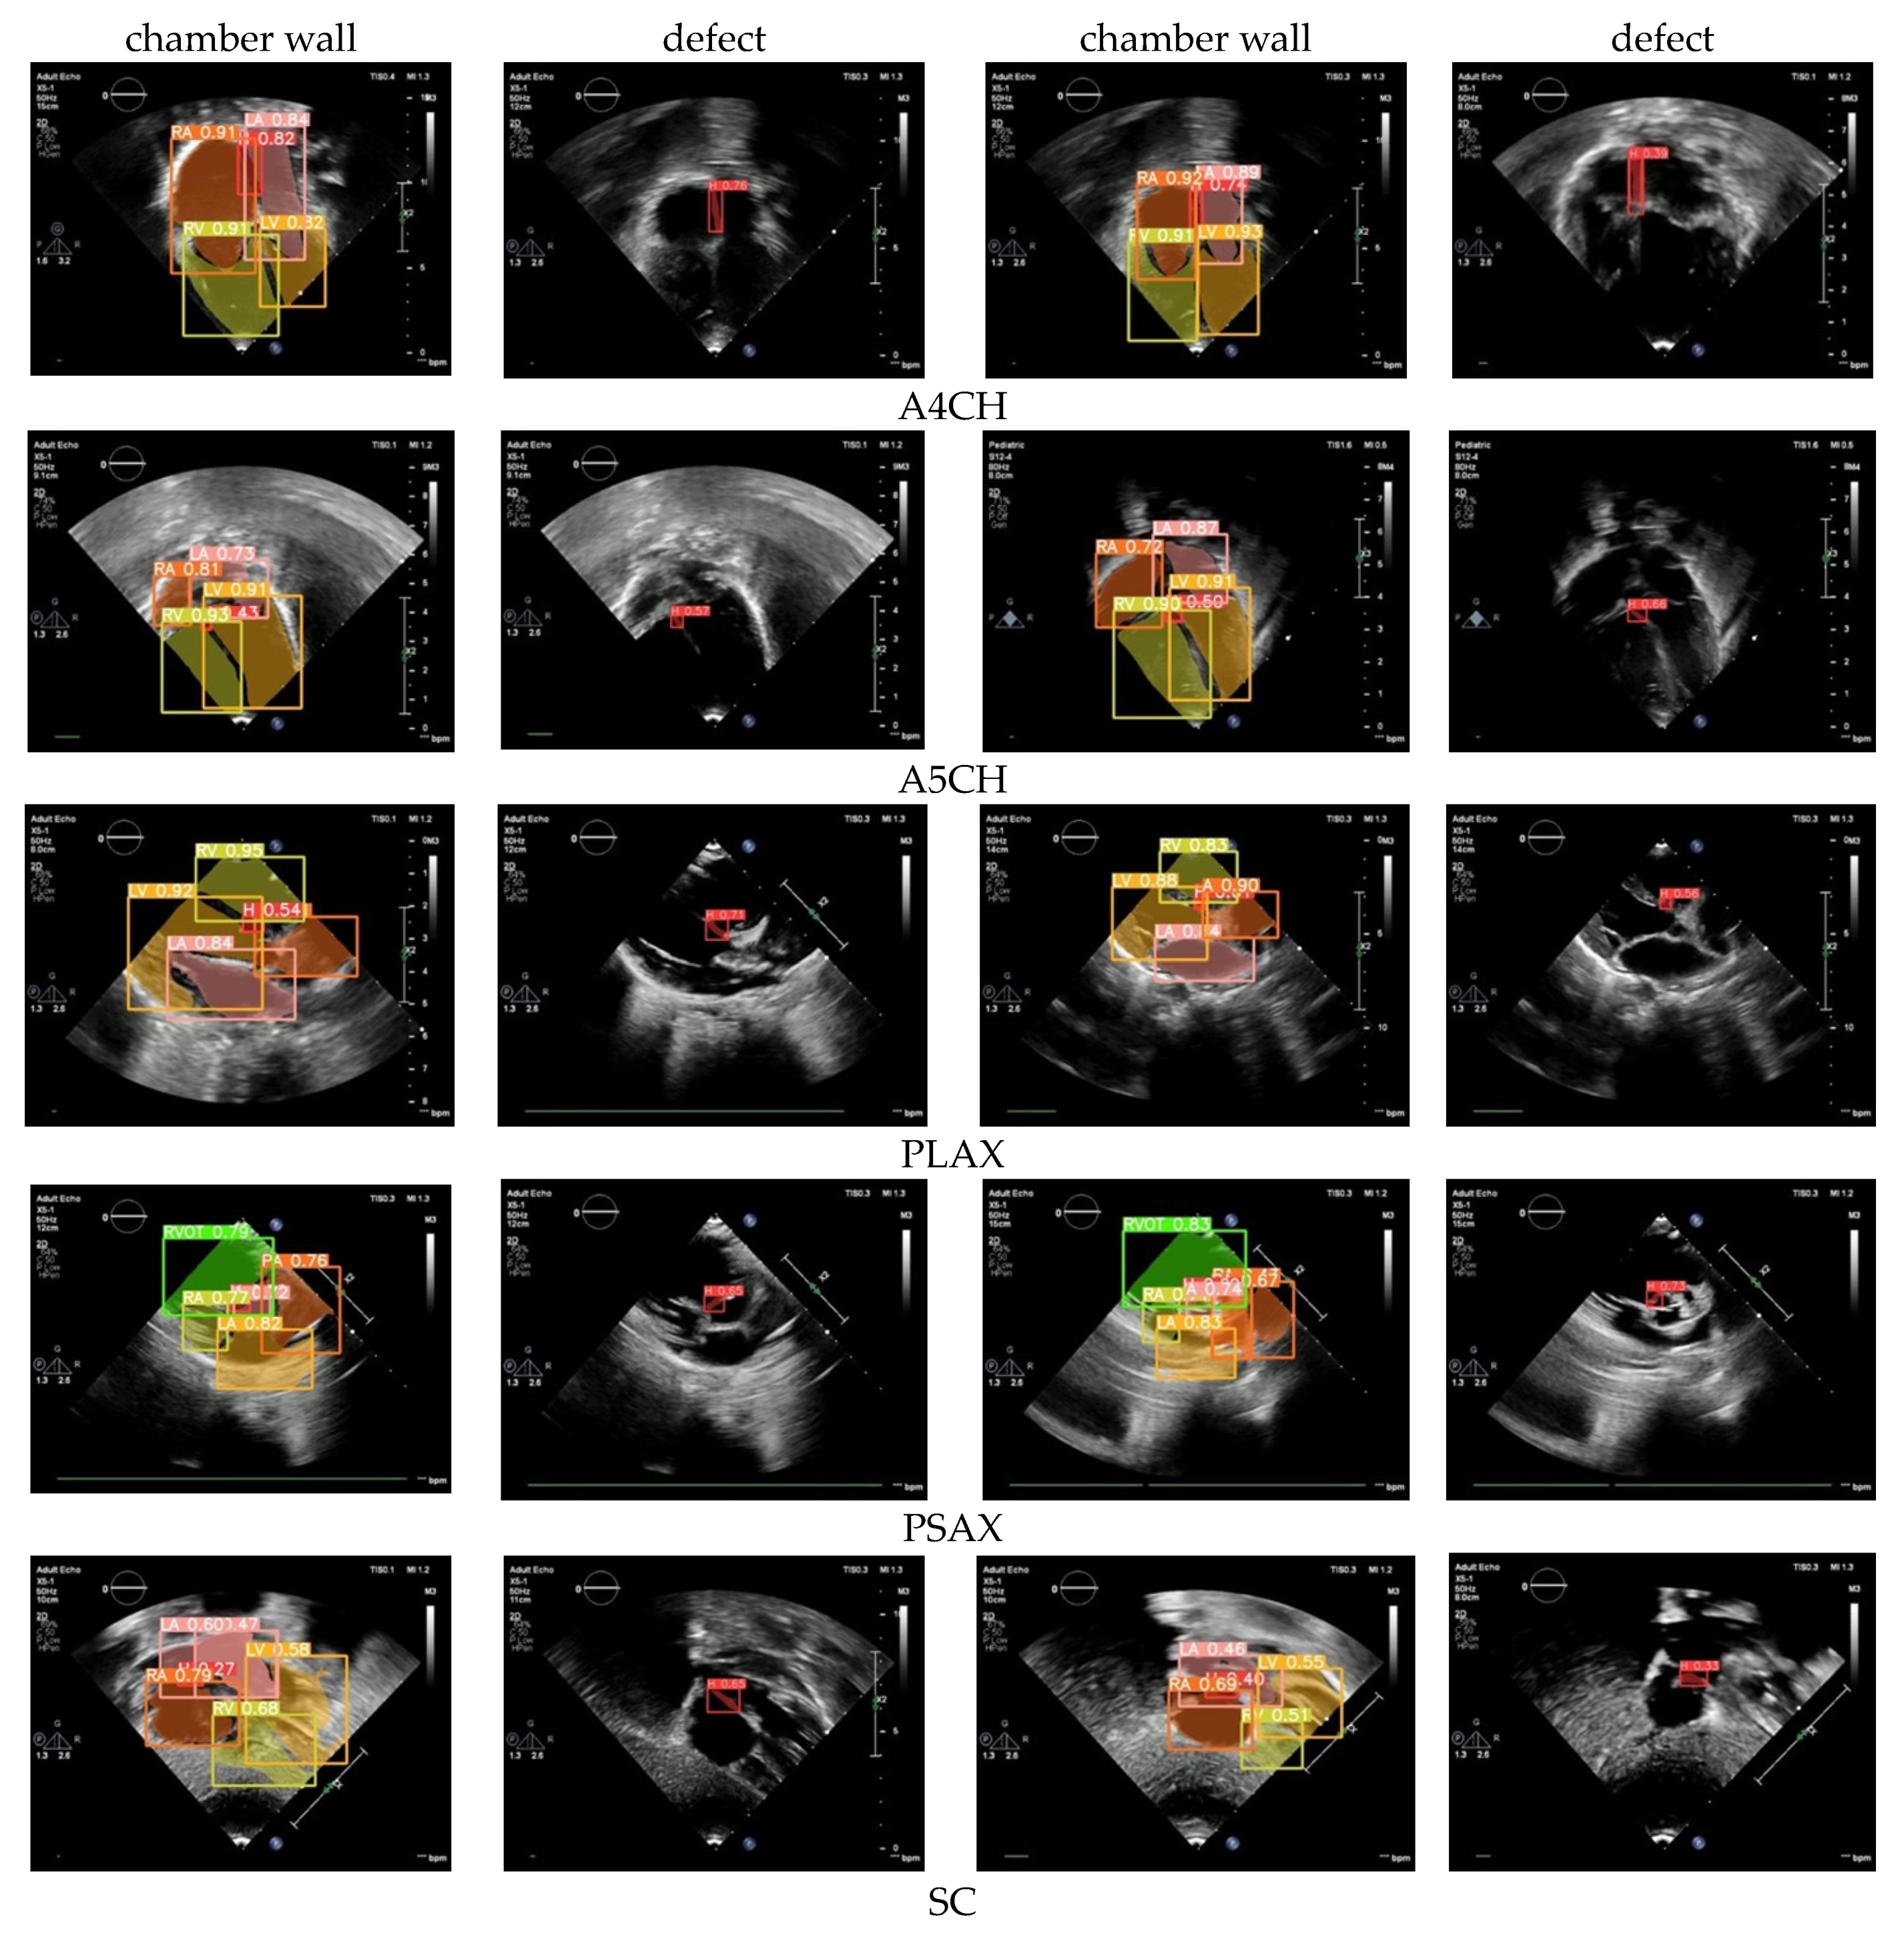

2.2.3. Defect Detection

The standard cardiac view of US video recordings has consisted of A4CH, A5CH, PLAX, PSAX, and SC. Pediatric cardiologists rely on specific views when assessing a patient’s condition. The annotation of the three CSD conditions is presented in Figure 3 using LabelMe 5.3.1 software. The annotated sample results in showcasing the chamber wall area and the cardiac defect area. Atrial or ventricular areas are represented by the white regions, while the red region denotes a cardiac defect area.

Figure 3.

Annotation of chamber wall and cardiac defect.

3.4. Defect Detection

Defect detection is the essential process of identifying and diagnosing anomalies within the heart. The timely detection of these anomalies is critical for initiating appropriate treatment and effectively managing CSD conditions, which can profoundly influence a child’s health and overall well-being. Based on the normal–abnormal and view classification results, we employed Yolov8l to perform defect detection. The mAP was utilized to assess the performance of both the validation and unseen data. We utilized the five standard cardiac views to ensure thorough results: A4CH, A5CH, PLAX, PSAX, and SC. These views play a pivotal role in precisely evaluating the cardiac chamber wall classes, including RA, RV, LA, LV, and identifying any septal defects (H) within the heart (Figure 8).

Figure 8.

The CSD detection performance using our framework on five standard views.

Chamber wall detection (LA, RA, LV, RV) across the five views yielded satisfactory results, both in terms of the validation and unseen data, with the mAP value exceeding 90%. However, in the defect detection or hole (H) detection, the mAP average value dropped below 85%. The A4CH and SC views successfully detect with a mAP of over 80%, whereas A5CH, PLAX, and PSAX only achieve mAP values below 65% for the validation data and below 60% for the unseen data. It can be observed that achieving accurate detection in both the A4CH and A5CH views poses significant challenges due to their similarity. The main point of differentiation in the A5CH view is the presence of the aorta in the middle of the chamber wall. As a result, errors are quite common during both the validation and unseen test phases. The parasternal view (PLAX and PSAX) provides a longitudinal slice of the heart, which may not offer a comprehensive view of all the cardiac structures. Certain defects, especially those located in less visible areas or those requiring a different angle of approach, may not be easily detected. However, achieving a mAP value greater than 50%, the model demonstrated the effective detection of cardiac defects.

3.7. The CSD Visualization

Detecting defects can be challenging due to the heart being a complex three-dimensional organ with intricate structures. Some defects may be subtle or located in areas where they are obscured by other cardiac structures, making them difficult to identify from a single imaging plane. Our framework uses a combination of five views to make a CSD decision. A visualization of our results to show an object detection scheme on the chamber wall and hole is shown in Figure 10. There are walls that separate the chambers, and each chamber has its own walls. The septum is the primary wall that divides the cardiac into left and right sides. There is the interatrial septum between the atria and the interventricular septum between the ventricles. LA, LV, RA, RV are objects that must be detected on the chamber wall, so as to assist in determining the position of defects or holes. By identifying the position of defects or holes in these walls, it helps in diagnosing the type of CSD.

Figure 10.

The sample of CSD detection images in five views.

The value obtained in each image represents the confidence level of the detection results. For the purposes of this study, a confidence value exceeding 0.5 can be deemed indicative of a reliable decision. It can be observed that all the confidence values are above the baseline value, meaning that the proposed Yolov8l model is capable of exhibiting a reliable detection performance for defects in the cardiac septum.